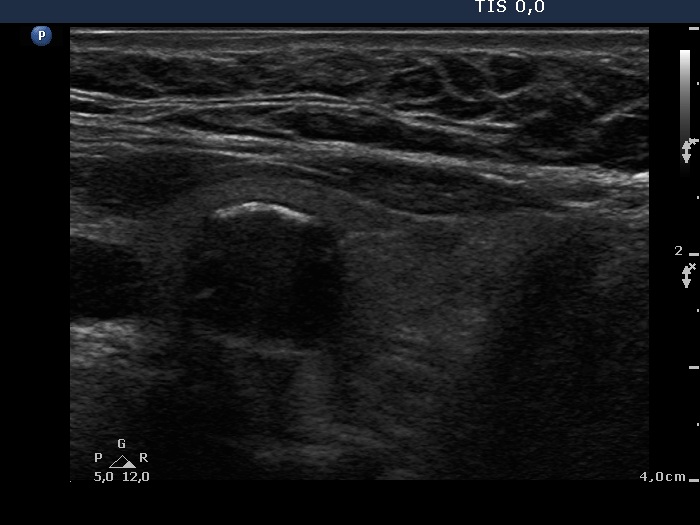

Benign colloid goiter (cytological diagnosis)

This nodule presents different types of hyperechogenic granules, the ventral figures are either comet-tail artifacts or punctate echogenic foci, while although the primary focus cannot be seen, the acoustic shadows prove that there are coarse calcifications, as well.